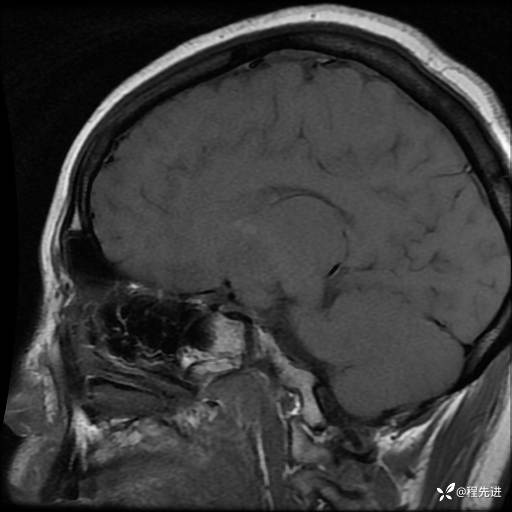

MRI平扫+增强:

T1: